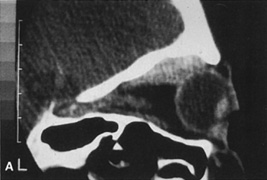

TRANSANTRAL ORBITOTOMY

Lesions in the subperiosteal space that involve the orbital floor and roof of the maxillary sinus can be approached through an intraoral incision in the buccal sulcus above the upper canine incisors (Fig. 19). Dissection is carried through mucosa and soft tissue to the periosteum over the face of the maxilla. Dissection is carried superiorly in the subperiosteal plane to just below the inferior orbital rim. Care must be taken to identify the infraorbital nerve as it exits the foramen just below the rim. Osteotomies then are made in the face of the maxilla, and the underlying maxillary sinus is exposed. The sinus mucosa is excised and the roof of the sinus exposed in this fashion. Removal of the sinus roof (the orbital floor) allows exposure of the inferior periorbita. Care must be taken to avoid damage to the infraorbital nerve that runs within the bone of the floor. The inferior rectus muscle is encountered immediately above the periorbita, and it must be protected and retracted during deeper orbital dissection.

Fig. 19. Transantral inferior orbitotomy. The orbital floor (A) (roof of maxillary sinus) is exposed by an incision in the buccal sulcus and removal of the anterior face of the maxillary bone. The infraorbital nerve (B) traverses the floor of the orbit and exits on the face of the maxilla from the infraorbital foramen (C).